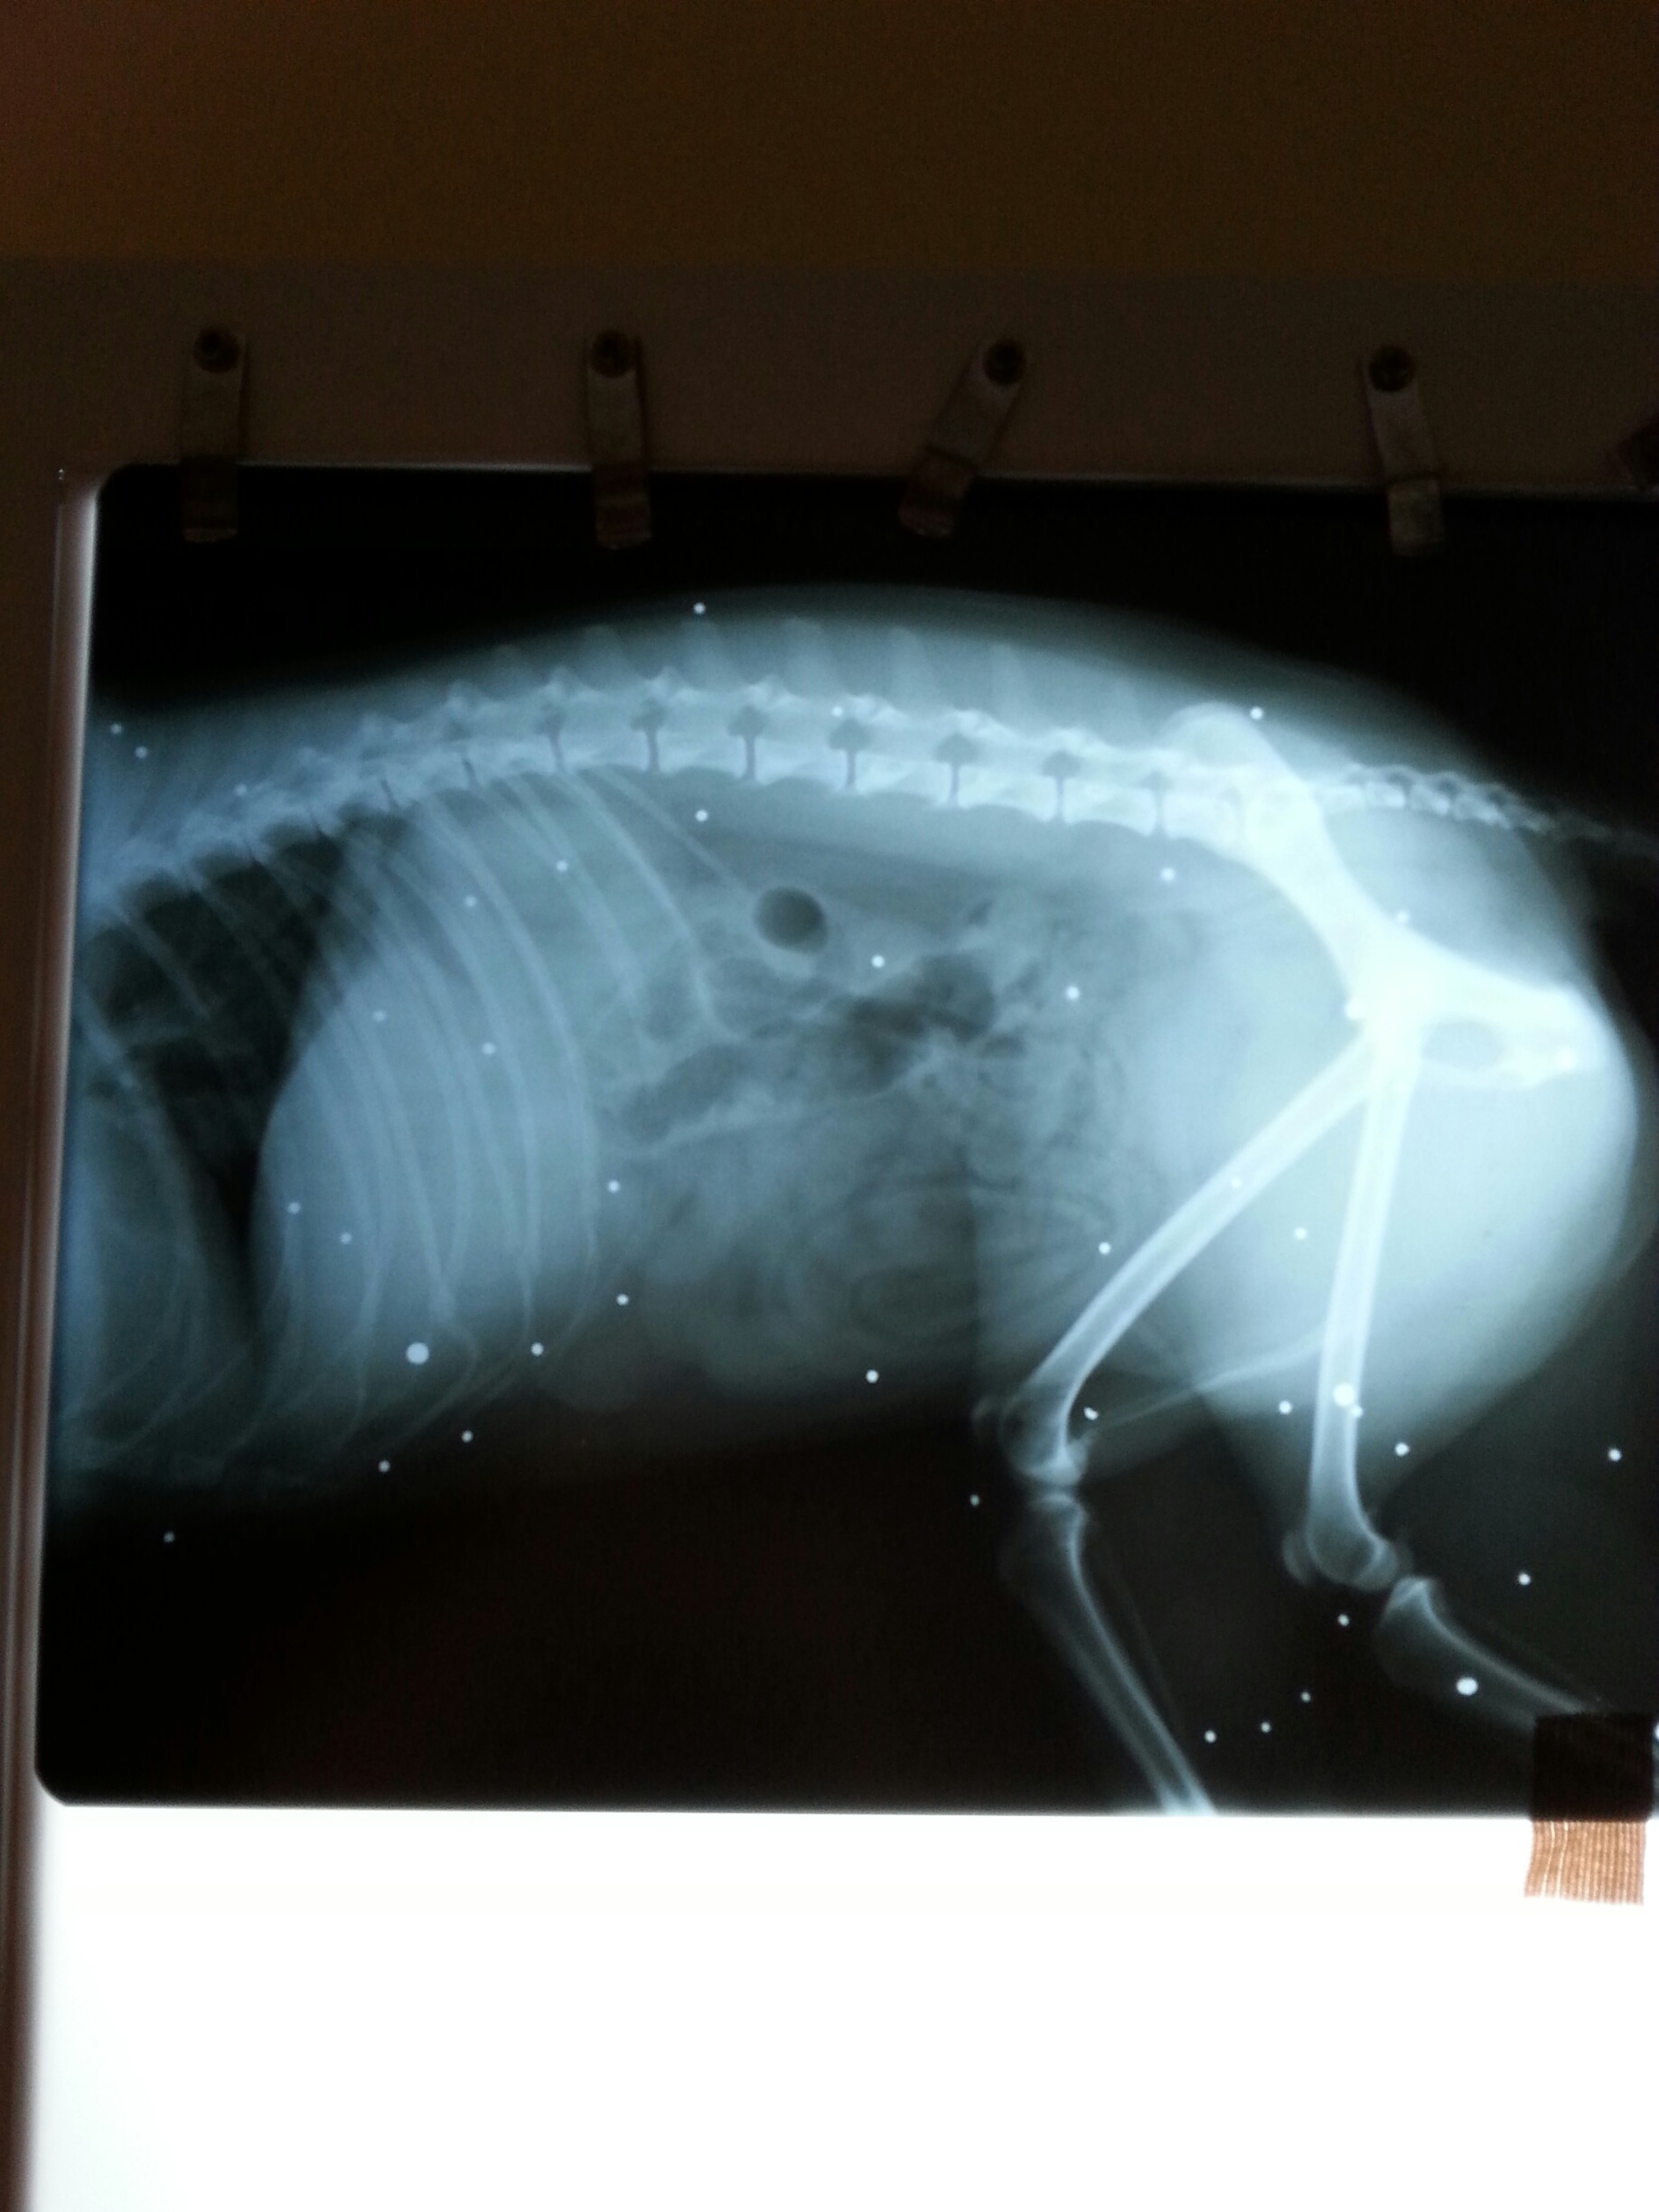

Sehen Sie selbst, was der Tierarzt bei Röntgenaufnahmen festgestellt hat: Bild 1+2 |

Ein schiesswütiger grausamer und gedankenloser Jäger hat auf Misty gezielt und ihn so voller Schrot geballert, dass man die Kugeln kaum zählen kann. Sie sitzen am Knochen, in den Organen, in den Muskeln und in der Haut. Dass Misty das überlebt hat, grenzt an ein Wunder. Die Bleikugeln haben sich in seinem kleinen schmächtigen Körper verkapselt und können nicht herausoperiert werden. Wer bitte kann Misty helfen?